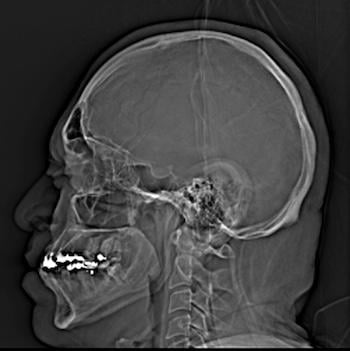

A new study shows large increases in the use of computed tomography (CT) scans of the head in emergency departments across the United States from 2007 to 2022. The study, which was published on Nov.19, 2025, in Neurology, the medical journal of the American Academy of Neurology, also found disparities in use of head CTs by race, type of insurance and hospital location.

“Head CT scans are a critical tool for diagnosing neurological emergencies, but their growing use raises concerns about cost, radiation exposure and delays in the emergency department,” said study author Layne Dylla, MD, PhD, of Yale School of Medicine in New Haven, Connecticut. “It’s important to balance the benefits of these scans with the risks and costs.”

For some situations, CT scans are considered unnecessary, as guidelines have shown that the images add little value to diagnosis but bring additional costs and radiation exposure. However, in other situations, CT scans are critical for time-sensitive diagnoses and treatments.